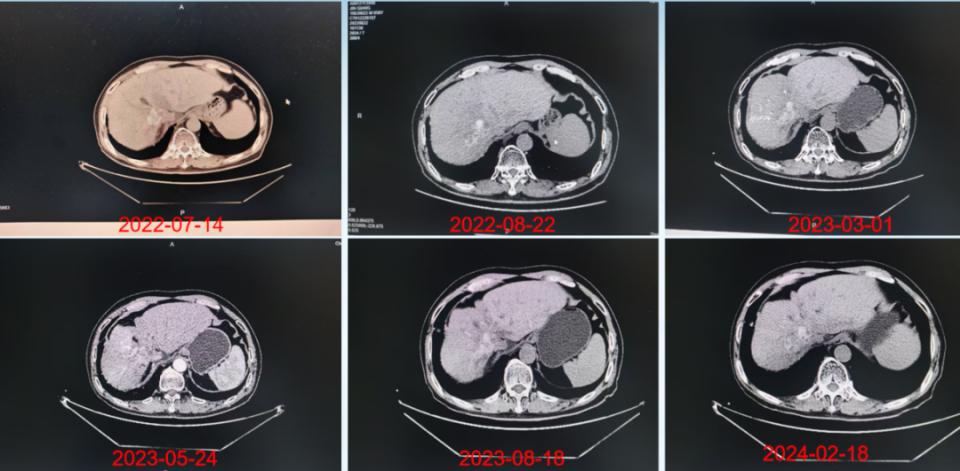

治疗随访期间肝脏CT影像学的变化

注:2022-07-14(胸部CT显示:肝右叶占位,其内少许碘油沉积/出血可能,肝左叶结节状致密影)。2022-08-22(对比2022-07-14胸部CT,肝癌介入术后改变,肝右叶占位,体积较前稍缩小、仍强化)。2023-03-01(对比2022-8-22胸部CT,肝癌介入术后改变,肝右叶碘油沉积较前减少,术区病灶活性残存)。2023-05-24(上腹部CT增强:对比2023-3-1CT,肝癌介入术后改变,肝右叶碘油沉积较前减少,术区病灶活性残存可能)。2023-08-18(对比2023-05-24日CT片,肝癌介入术后改变,肝右叶碘油沉积,术区病灶活性残存)。2024-02-18(对比2023-08-18日CT片,肝癌介入术后改变,肝右叶碘油沉积,术区病灶活性残存)。

注:2024-05-20(胸部CT扫描:临床提示肝恶性肿瘤放疗后,肝左右叶胆管交界处可疑增多软组织影,肝内胆管扩张,胆管细胞癌?其内多发斑片状高密度影,胆管结石?出血?)。2025-02-05(对比2024-02-18日CT片,肝癌介入术后改变,肝右叶碘油沉积,术区病灶活性残存)。2025-08-11(肝癌介入术后病史,对比2023-05-24上腹部增强CT、胸部CT,肝癌介入术后改变,肝右叶病灶范围较前稍增大并不均匀强化,提示活性残存可能,其内碘油沉积稍减少)